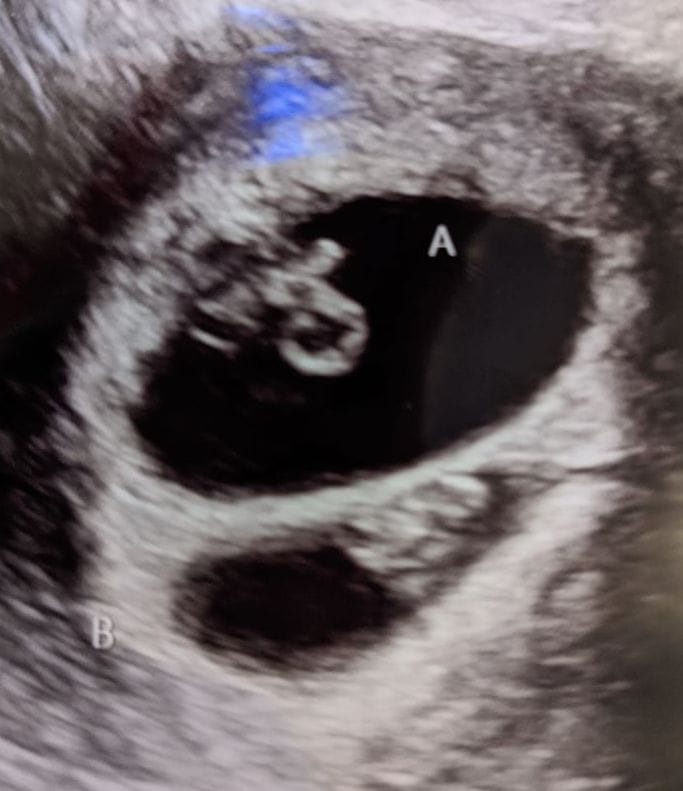

Early Twin Ultrasound at 7 Weeks

The earliest your doctor would likely order an ultrasound confirming twins would be 4 weeks pregnant. But unless you are going through fertility treatments, doing an ultrasound before 6 weeks isn’t very common, with the exception of complications. Women who are going through fertility treatments or have early complications may be able to have an early twin ultrasound at 4 or 5 weeks pregnant and find out they are pregnant with twins.

At four to five weeks after a pregnant woman’s last period the ultrasound commonly shows a small collection of fluid within the lining of the uterus that represents the early development of the gestational sac. At about five and a half weeks after a pregnant woman’s last period the ultrasound typically shows a gestational sac and within it we can see a 3-5 mm bubble-like structure, which is the yolk sac. At approximately six weeks after a pregnant woman’s last period, we can see a small fetal pole, one of the first stages of growth for an embryo, which develops alongside the yolk sac.

Can You Tell at 7 Weeks if Its Twins?

Yes! You’d need to have an ultrasound at 7 weeks to confirm a twin pregnancy. Your twin belly at 7 weeks may not look like much of a belly at all, so getting in to your doctor for an ultrasound is key to find out if you’re really having twins.